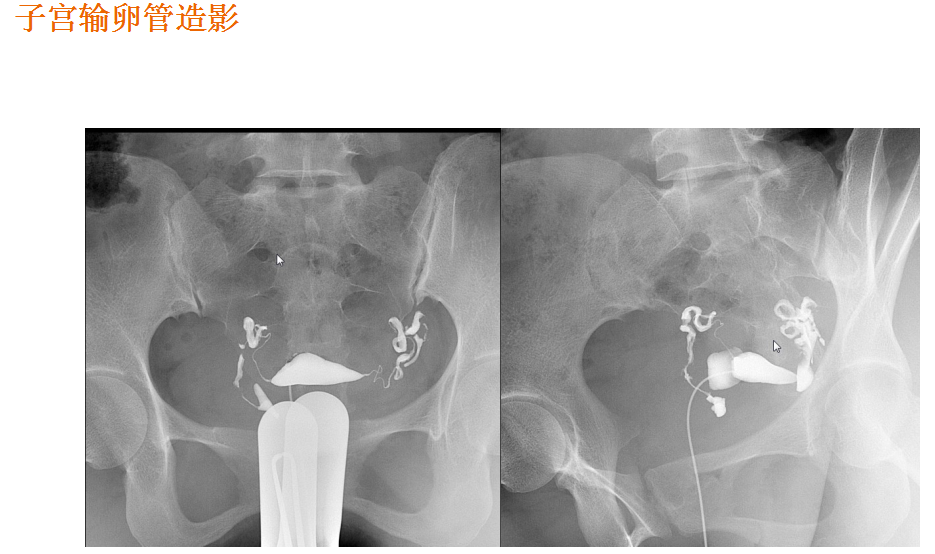

该设备属于多功能X线机,除具有传统数字胃肠机所有功能外,还有DR平板探测器X线摄影所有功能,主要用于消化道气钡双重对比造影、全脊柱拼接摄影、全下肢拼接摄影、ERCP、泌尿系造影、“T”管造影、钡剂灌肠、四肢造影、子宫输卵管造影等各类检查,是检查消化道溃疡、肿瘤、异物等疾病的主要方法之一。

在临床方面,强大的图像处理功能可以完成临床各种造影的需求。